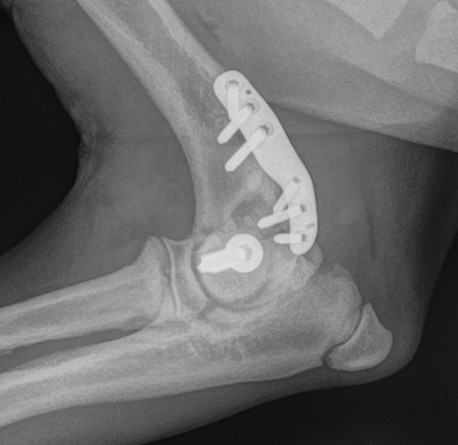

Practical Repair of Humeral Intracondylar Fissures and Condylar Fractures - 30 APR 2026Info Course Information![]() Practical Repair of Humeral Intracondylar Fissures and Condylar Fractures This CPD event will train vets to surgically manage humeral intracondylar fissures (HIF) and humeral condylar fractures (HCF). Procedural videos will be issued prior to the event, and the day itself focuses on maximising practical surgical exposure, using drybones and cadavers to ensure the specifics of implant placement are understood before being applied in a lifelike surgical context. In the last decade, implant systems for management of HIF and HCF have advanced dramatically, allowing more repeatable surgical procedures and more reliable surgical outcomes. This CPD event uses Fusion Implants, including the Humeral Intracondylar Repair system (HIRs) and the Lateral Epicondylar Anatomic Plate (LEAP), with technical support from Fusion available at all times